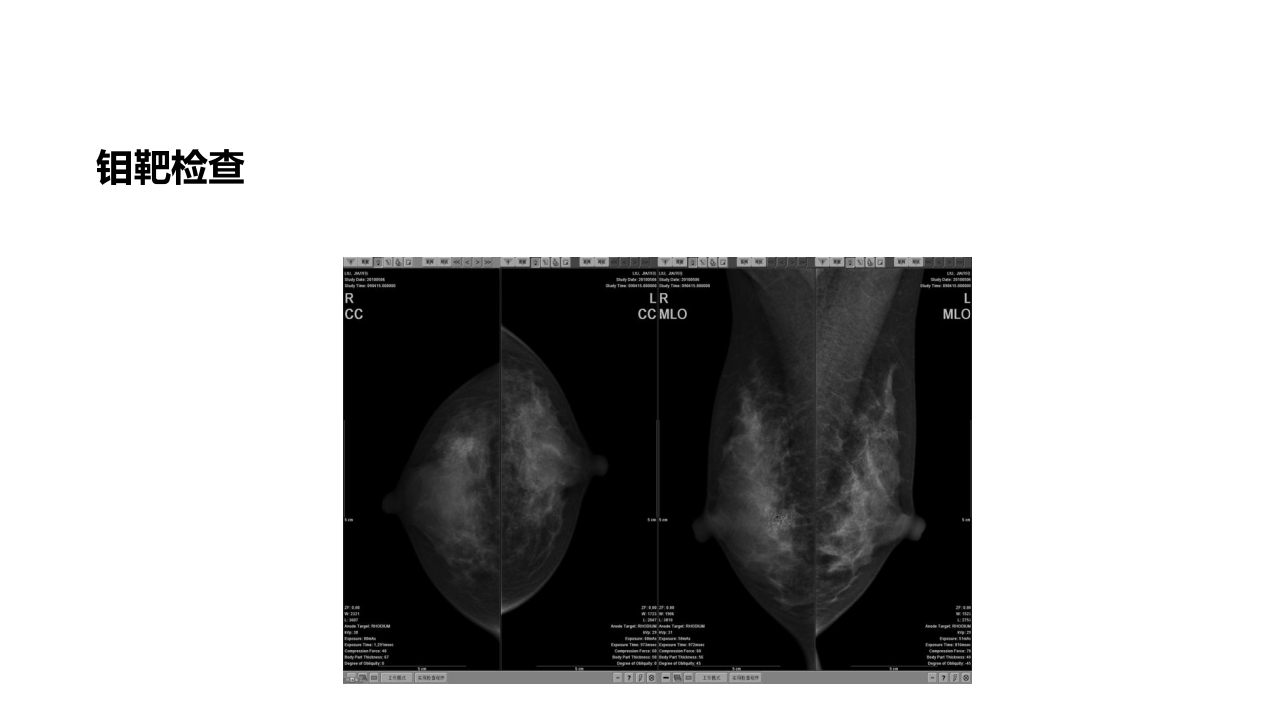

乳腺癌的护理 ENGINEERING 03 汇报人:xxx 日期:2024.10.10 CONTENTS 目录 壹 贰 叁 掌握乳腺癌术后护理要点 Pleaseaddaclearbusinesstemplateforth etitlecontentyouwantoaddPleaseaddacl earbuPle 熟悉乳腺癌的相关检查 Pleaseaddaclearbusinesstemplateforth etitlecontentyouwantoaddPleaseaddacl earbuPle 了解乳房重建的手术方式 Pleaseaddaclearbusinesstemplateforth etitlecontentyouwantoaddPleaseaddacl earbuPle 壹 掌握乳腺癌术后 护理要点 一、病史汇报 25床,XXX,女,XXX岁,住院号:XXXXXX, 学历:小学,家庭条件一般。 患者系“左乳癌术后二年,右乳包块8月余”, 门诊拟“左乳癌术后,右乳包块”于20XX.X.5 收住入院。 既往史:XX年因“左乳癌”行“左乳改良根治 术 ...